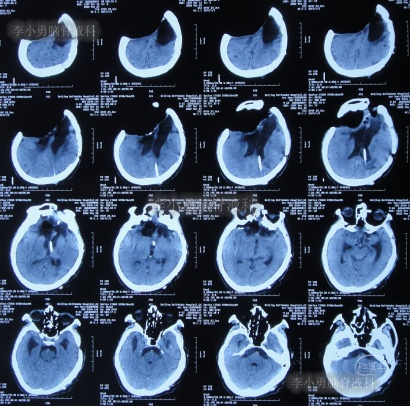

2012年11月1日(开颅术后126天即脑室腹腔分流术16天),转住入李小勇脑脊液科入院时:神志模糊,表情淡漠,肢体不能遵嘱活动,时常有癫痫发作;右额颞顶颅骨缺损,缺损相应区域局部凹陷,自右侧鼻唇沟至头顶有一疤痕,右侧额面部颅骨凹陷(图-6)。头颅CT:脑室腹腔分流术后改变,脑室扩张(图-7)。

图-7:入院时头颅CT

术后次日查头颅CT示脑室外引流术后(图-8);血培养(厌氧菌):溶血葡萄球菌感染。

图-8:2012年11月6日头颅CT

2012年11月23日(入院治疗23天),引流出血红色脑脊液(图-9);查头颅CT示脑室有缩小(图-10)。

图-10:2012年11月23日头颅CT

2013年1月14日(入院治疗75天),进行了左侧脑室腹腔分流术(图-11);

图-11:2013年1月14日术后头颅CT

2013年1月17日(入院治疗78天),晚上19点左右,患者突发意识障碍、右侧肢体偏瘫,头部外引流管流出粉红色液体,急查头颅CT示左额颞顶区硬膜下血肿,蛛网膜下腔出血(图-12)。于当晚急诊全麻下进行“左额颞顶硬膜下血肿清除术”。

图-12:2013年1月17日头颅CT

术后患者仍处于昏迷状态;次日2013年1月18日晨起,颅骨缺损处张力较高,复查头颅CT示术区无明显再出血,左顶叶硬膜外血肿,术区脑组织肿胀(图-13),当天进行了左额颞顶硬膜下血肿清除术后,左顶叶硬膜外血肿(图-14)。

图-13:2013年1月18日头颅CT

图-14:2013年1月18日术后头颅CT

2013年1月22日(入院治疗83天),患者术区引流管引流液极少,复查头颅CT脑室较前稍有扩张,右侧骨窗张力仍较高(图-15),进行了侧脑室外引流术(右)+左额颞顶硬膜下引流管去除术+左顶硬膜外引流管去除术。

图-15:2013年1月22日头颅CT

2013年1月25日(入院治疗86天),查头颅CT示脑室有缩小(图-16)。

图-16:2013年1月25日头颅CT

2013年1月31日(入院治疗92天),查头颅CT示脑室进一步缩小,骨窗塌陷(图-18)。

图-18:2013年1月31日头颅CT